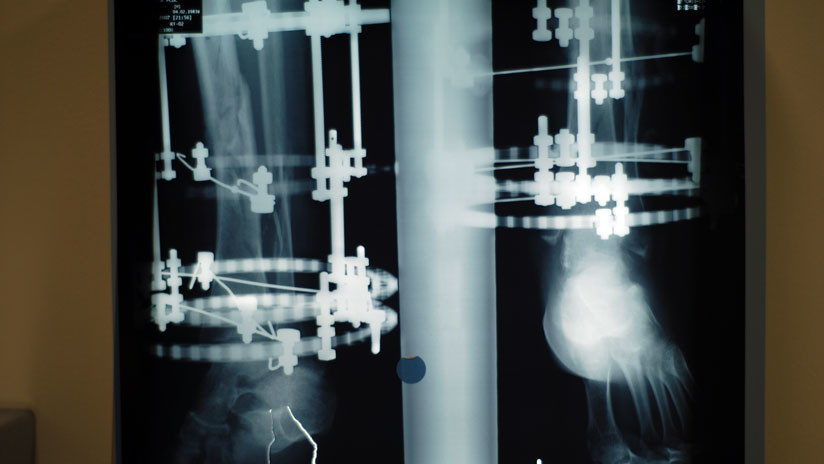

Dicha innovación puede emplearse en la cura de patologías congénitas, como extremidades acortadas, en cuyo caso el miembro reducido es elongado con ayuda del aparato fijador externo Ilizárov. Como resultado aparece nuevo tejido óseo, que de engendrarse mal puede recibir inyecciones de células madre para acelerar la osteogénesis.

Imagen ilustrativa / Radiografía de pierna con aparato Ilizárov.